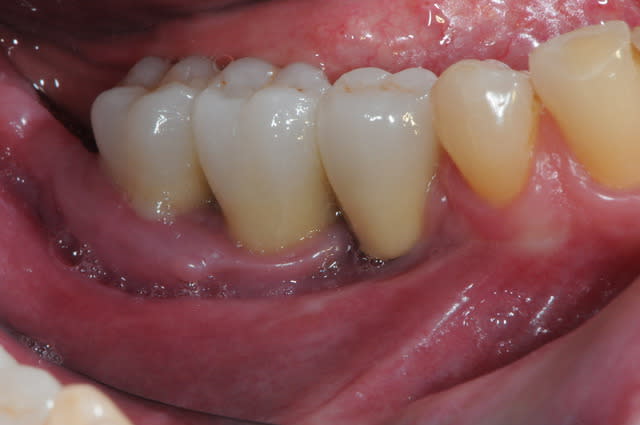

1-2

enfin, mise en place d'une membrane péricarde Jason de 30*50 (je crois)

3- j'ai profité de la stabilité de la mesh comme piquet de tente pour bourrer la cavité avec du MAXGRAFT (os humain)..

4-5- un peu de A-PRF (the king !)

6- le plus important des sutures hermétiques et une gencive immobile en fin d'intervention

7 les radios post-op